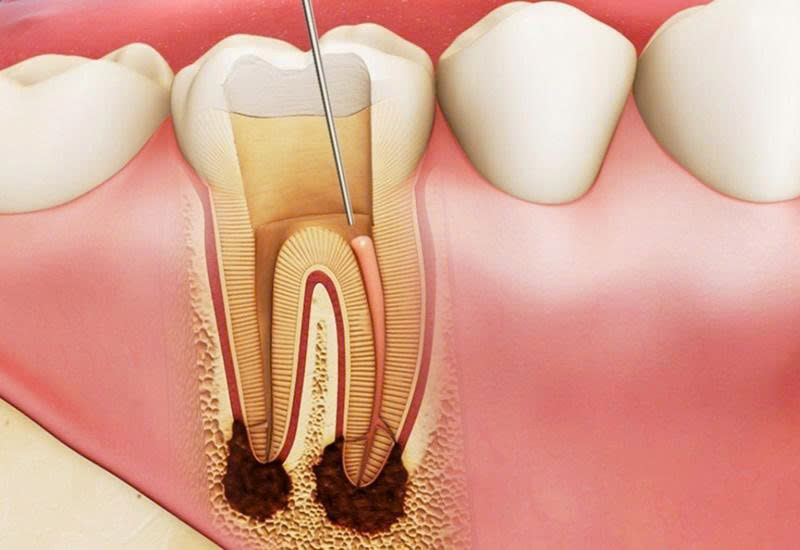

🔹 Điều trị tủy là gì?

Điều trị tủy (Root Canal Treatment) là quá trình bác sĩ loại bỏ phần tủy bị viêm hoặc hoại tử, làm sạch – tạo hình – trám bít ống tủy, sau đó phục hồi lại thân răng bằng trám hoặc bọc sứ.

🔹 Quy trình điều trị tủy chuẩn tại Nha Khoa SV

-

Khám và chụp phim X-quang:

Bác sĩ kiểm tra tổng quát, chụp phim để xác định tình trạng tủy và số lượng ống tủy. -

Gây tê và cách ly răng:

Sử dụng thuốc tê thế hệ mới giúp quá trình điều trị hoàn toàn êm ái. -

Loại bỏ phần tủy viêm:

Dùng thiết bị nội nha hiện đại giúp làm sạch nhẹ nhàng, chính xác. -

Làm sạch và tạo hình ống tủy:

Dùng dung dịch sát khuẩn chuyên dụng, tạo hình chuẩn xác. -

Trám bít ống tủy:

Dùng vật liệu gutta-percha chuyên biệt để bít kín, ngăn vi khuẩn xâm nhập. -

Phục hồi thân răng:

Tùy tình trạng, bác sĩ sẽ trám hoặc bọc sứ bảo vệ răng lâu dài.